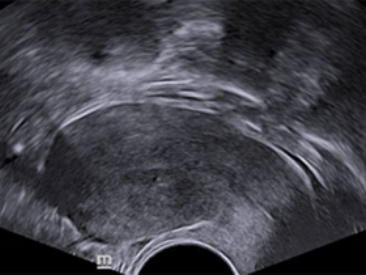

Images cliniques